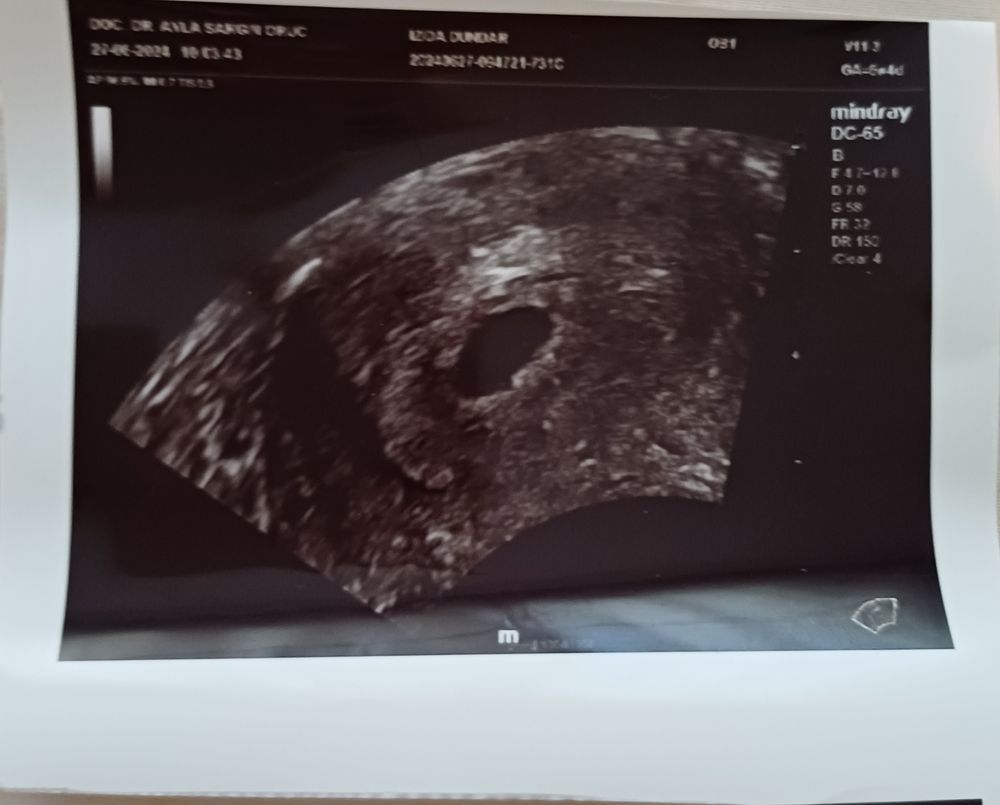

Так как не доверяю одному мнению поехали к другому врачу. Этот доктор сказал немного мало на зато выросло по сравнению с прошлой неделей хорошо ( ровно неделю назад было 3,4 мм) смотрел более внимательно в итоге нашёл мерцающую точку, это говорит кровопоток и возможно эмбрион просто ему ещё немного времени нужно. Сказал подождать ещё неделю и посмотрим из препаратов назначал - Прогестерон 200 свечи 2 раза в день, Дюфастон, Оксапар для улучшения кровопотока и помощи малышу. Говорит шансы 50/50